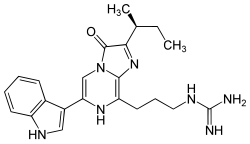

Vargulina o Cypridina luciferina (IUPAC= 2-[3-[2-[(2S)-butan-2-il]-6-(1H-indol-3-il)-3-oxo-7H-imidazo[2,1-c]pirazin-8-il]propil]guanidina) es la luciferina que se encuentra en el ostrácodo Cypridina hilgendorfii también llamado Vargula hilgendorfii.[1][2][3] y permite la emisión de una luz azul

- Fórmula molecular = C22H27N7O

- Masa molar = 405.496